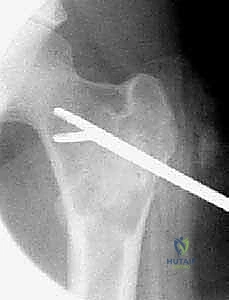

ثانياً: التدخلات طفيفة التوغل (الحقن)

يُفضل هذا الخيار غالباً لحالات كيس العظم أحادي الغرفة (UBC) لتجنب الجراحة المفتوحة، خاصة عند الأطفال الصغار.

* حقن الكورتيكوستيرويد (Steroid Injections): يتم إدخال إبرتين تحت توجيه الأشعة السينية (Fluoroscopy). تُستخدم الإبرة الأولى لشفط السائل الكيسي، والإبرة الثانية لحقن مادة الكورتيزون (Methylprednisolone). يعمل الكورتيزون على تثبيط الخلايا المسببة لتآكل العظم، مما يسمح للعظم بالشفاء. قد يتطلب الأمر تكرار الحقن 2-3 مرات بفاصل بضعة أشهر.

استخدام تقنيات الحقن طفيفة التوغل تحت توجيه الأشعة السينية المباشرة، وهي خطوة أولى فعالة في علاج أكياس العظام أحادية الغرفة (UBC) لتجنب الجراحة المفتوحة متى ما أمكن ذلك.